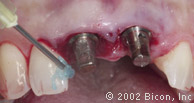

Установка двух 5.0mm x 8.0mm HA имплантантов Bicon

Определение направления оси и глубины шахты имплантантов

Abutment Shoulder Gauge

Вид после установки